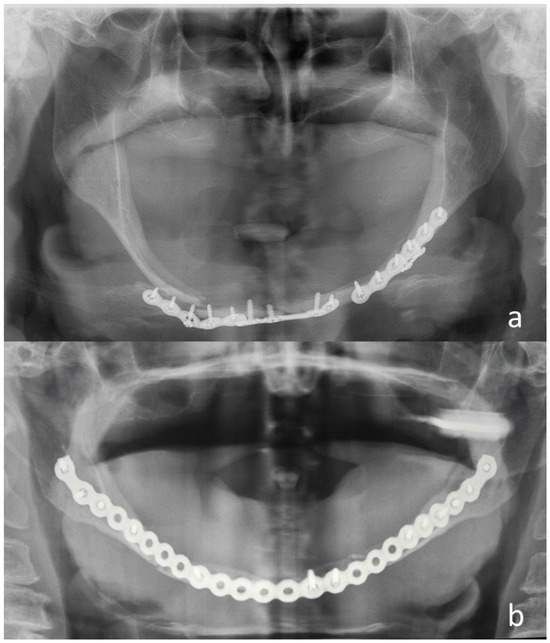

| N | Sex | Age | Etiology | Mandibular Fracture Sites Associated | Atrophy Degree * | Approach | Treatment | Hospitalization (Days) |

|---|---|---|---|---|---|---|---|---|

| 15 | F | 76 | Fall | None | III | Extraoral | 2 plates 1.0 mm bilateral | 3 |

| 16 | F | 80 | Fall | None | III | Extraoral | Plate 2.0 mm | 5 |

| 17 | F | 80 | Fall | None | III | Extraoral | 1 plate 1.5 mm right 1 plate 1.0 mm left | 5 |

| 18 | F | 81 | Fall | Symphysis | III | Extraoral | 1 plate 1.5 mm bilateral | 6 |

| 19 | F | 81 | Fall | None | III | Extraoral | Plate 2.0 mm | 11 |

| 20 | F | 82 | Fall | Symphysis | III | Extraoral | Plate 2.0 mm | 4 |

| 21 | F | 84 | Fall | None | III | Extraoral | Plate 2.0 mm | 6 |

| 22 | F | 84 | Fall | None | III | Extraoral | Plate 2.0 mm | 8 |

| 23 | F | 85 | Fall | None | III | Extraoral | Plate 2.0 mm | 7 |

| 24 | F | 87 | Fall | None | III | Extraoral | Plate 2.0 mm | 7 |

| 25 | M | 90 | RTA | None | III | Extraoral | Plate 2.0 mm | 4 |

| 26 | F | 94 | Fall | None | III | Extraoral | Plate 2.0 mm | 7 |

| Dentate Patients n | Edentulous Patients n | p Value | |

|---|---|---|---|

| Age (years) | |||

| median (IQR) | 19.0 (26.0) | 80.0 (26.0) | <0.001 * |

| Cause | |||

| Assault | 0 | 1 (5%) | 0.008 ° |

| Fall | 0 | 15 (71%) | |

| Work | 1 (20%) | 2 (10%) | |

| RTA | 3 (60%) | 3 (14%) | |

| Sport | 1 (20%) | 0 | |

| Hospital stay (days) | |||

| median (IQR) | 5 (3) | 6 (3) | 0.801 * |

| Surgical approach | |||

| Intraoral | 5 (100%) | 3 (14%) | <0.001 ° |

| Extraoral | 0 | 18 (86%) | |

| Type of treatment | |||

| Plates 2.0 or 2.5mm | 0 | 12 (57%) | 0.042 ° |

| Plates 1.0 or 1.5 mm | 5 | 9 (43%) |